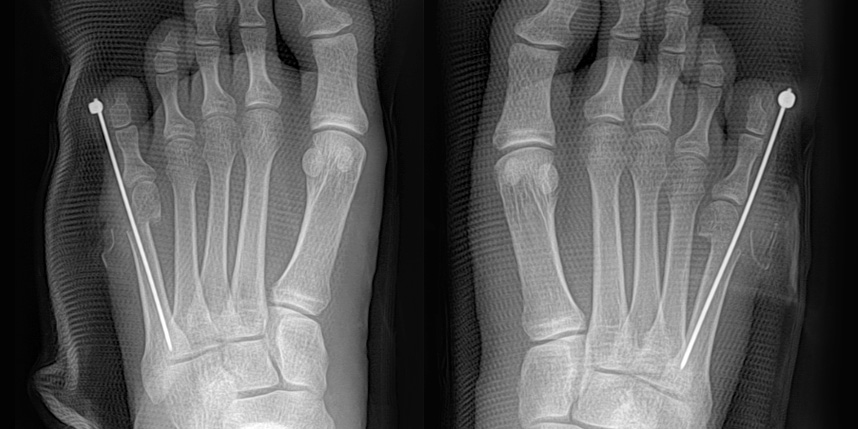

작은 구멍을 통해 초음파 절골기를 이용하여 뼈를 절골합니다.

중등도 이상의 큰 각도의 소건막류에도 충분히 적용이 가능합니다.

빨간 포탈을 이용하여 초음파 절골기를 삽입하여 절골을 하고 핀을 삽입합니다.

핀은 바깥으로 빼어 놓고, 6-8주째 외래에서 간단하게 제거합니다.

개방형 원위 절골술의 경우 절골 방법은 SERI 와 비슷하지만

조금 더 안정적이고 절개가 크지 않으면서 연부조직의 처리가 같이 가능하기 때문에 필요한 경우 적용할 수 있습니다.